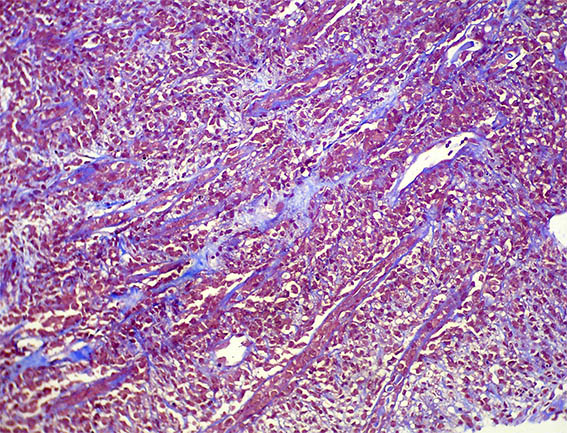

A renal allograft biopsy was done, see the images.

Figure 7. Masson's trichrome stain, X200.